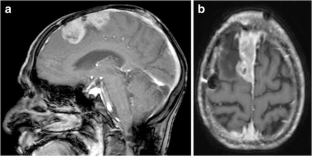

A 68-year-old man in good general health presented with a parasagittal meningioma that recurred following subtotal removal and adjuvant fractionated stereotactic radiosurgery (FSR). The scalp above the tumor location was very diseased and precluded a regular craniotomy for tumor removal. A 4-cm craniotomy was made in the midline forehead, where the skin was normal. A rigid endoscope was advanced under neuronavigation through the interhemispheric fissure, which provided good access with limited retraction, until the tumor was encountered at a depth of 7–8 cm. Two surgeons performed the surgery using a “four-hands technique”. The tumor was removed and the insertion area was resected and coagulated.

Fig. 2